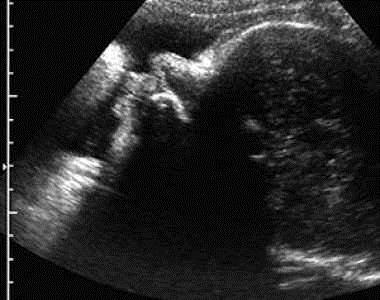

УЗД на 40 тижні вагітності